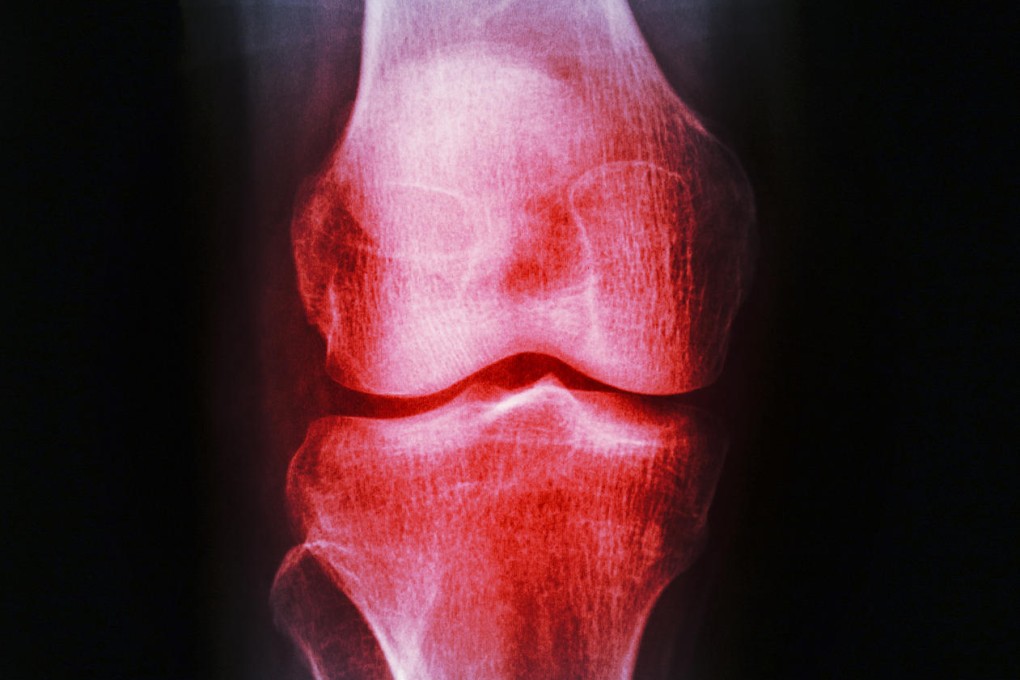

Yeung was diagnosed with osteoarthritis, the most common form of arthritis, which usually affects the knees, hip or hands. The pain happens when the cartilage, which normally covers the ends of your bones to absorb the shock of movement, gets worn down.